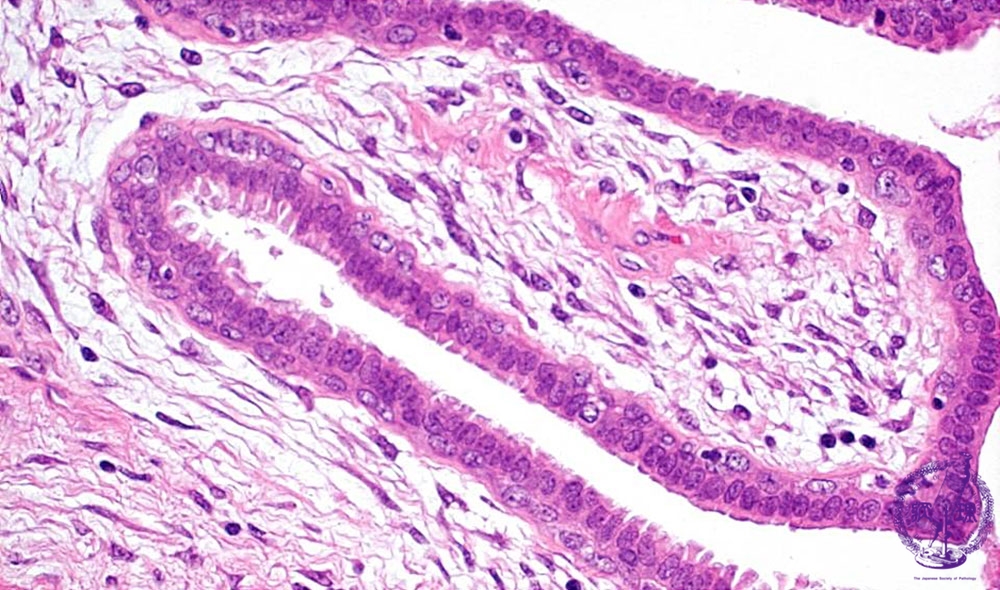

- ★(2)Fibroadenoma(intracanalicular type)

Microscopic image(HE stain, high power view):Tumor maintained distinctive bilayers of epithelial cells; 1)luminal columnar and 2) basal cells with clear cytoplasm (arrow). This finding usually suggestes a lesion that is benign in nature.